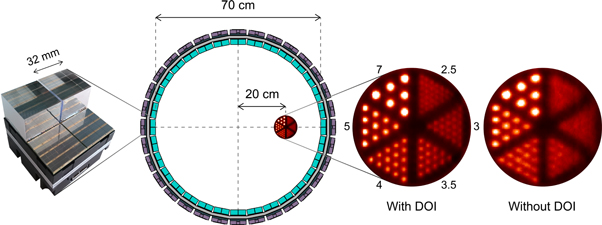

| DOI | Depth of interaction |

Standard image High-resolution imagePET image quality is affected by various sources of error (Cherry 2006, Lewellen 2008, Peng and Levin 2010). For example, the system intrinsic spatial resolution is determined by the finite range of the positrons (typically <1 mm), the accolinearity of the annihilation quanta (<0.5°), the finite crystal pitch (typically <5 mm), and parallax effects in case the depth of interaction (DOI) in the crystal is unknown and the annihilation occurs off-center (such as the true event in figure 1). The image signal-to-noise ratio (SNR) is determined for a large part by counting statistics and, consequently, is limited by the radiotracer dose, the scan time, and the system sensitivity. The first two factors should be kept as small as possible, so it is imperative to maximize sensitivity.

Indeed, the minimization of time resolution loss due to optical transfer kinetics is becoming an important research topic. All the more so, because the intrinsic rise time of the most commonly used TOF-PET scintillators (see table 1) and the SPTR of some photosensors are smaller than 100 ps already. The scintillator-photosensor geometry and the optical properties of the crystals, reflectors, light guides, and photosensors all affect  Intuitively, one would expect the use of larger crystals and/or complicated light-sharing schemes to broaden this distribution. Indeed, the best CRTs are often achieved with tiny crystals coupled one-to-one to photosensors, approaching the infinitesimal-crystal limit discussed previously. In fact, we have seen in section 2.3 that the optical transfer time distribution not only broadens in larger crystals, but that its mean and variance also become functions of the position of interaction

Intuitively, one would expect the use of larger crystals and/or complicated light-sharing schemes to broaden this distribution. Indeed, the best CRTs are often achieved with tiny crystals coupled one-to-one to photosensors, approaching the infinitesimal-crystal limit discussed previously. In fact, we have seen in section 2.3 that the optical transfer time distribution not only broadens in larger crystals, but that its mean and variance also become functions of the position of interaction  resulting in additional deterioration of the CRT (equation (18)). TOF-PET detector designs that enable the estimation of

resulting in additional deterioration of the CRT (equation (18)). TOF-PET detector designs that enable the estimation of  often called TOF/DOI detectors allow to (partially) recover the resulting loss of time information, as will be elaborated in sections 5.3 and 5.4.

often called TOF/DOI detectors allow to (partially) recover the resulting loss of time information, as will be elaborated in sections 5.3 and 5.4.